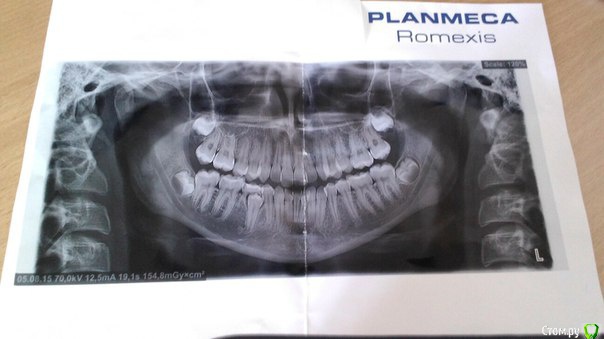

оля 75 Опубликовано 9 августа, 2015 Поделиться Опубликовано 9 августа, 2015 (изменено) девочке 14 лет,неровное расположение зубов(скученность),решили поставить брекеты,на снимке выявились молочный зуб и наклонные 8-ки.молочный зуб 3-дня назад удалили(удаление сложное,пришлось подпилить часть кости и высверливать корень молочного зуба(как объяснил стоматолог)),сейчас в месте удаленного зуба видны края кости и коронка нового зуба.мы решили основательно приступить к лечению зубов,перелопатили массу литературы и узнали,что наклонные 8-ки желательно удалить.пожалуйста,ответьте на вопросы:лучший ли будет вариант удалить данные 8-ки перед постановки брекетов в нашем случае,нужно ли удалять все четыре 8-ки,через сколько времени после удаления зубов мудрости лучше ставить брекеты,все равно будет требоваться сепарация зубов?,есть ли вариант удалить 8-ки после лечение брекетами или однозначно удалить перед брекетами?если не удалить 8-ки,поставить брекеты и 8-ки начнут прорезаться во время ношения брекетов,возможно ли их удаление в этот период?(у её папы 8-ки прорезались в 15 лет)наш ортодонт порекомендовала б/с деймон кью,хороша ли данная брекет-система?,лечение будет достаточно длительным и дорогостоящим,поэтому мы должны быть уверены что делаем для своего ребенка лучший выбор,и что-бы в будущем не было рецидива и проблем с зубами мудрости. Изменено 9 августа, 2015 пользователем оля 75 Ссылка на комментарий